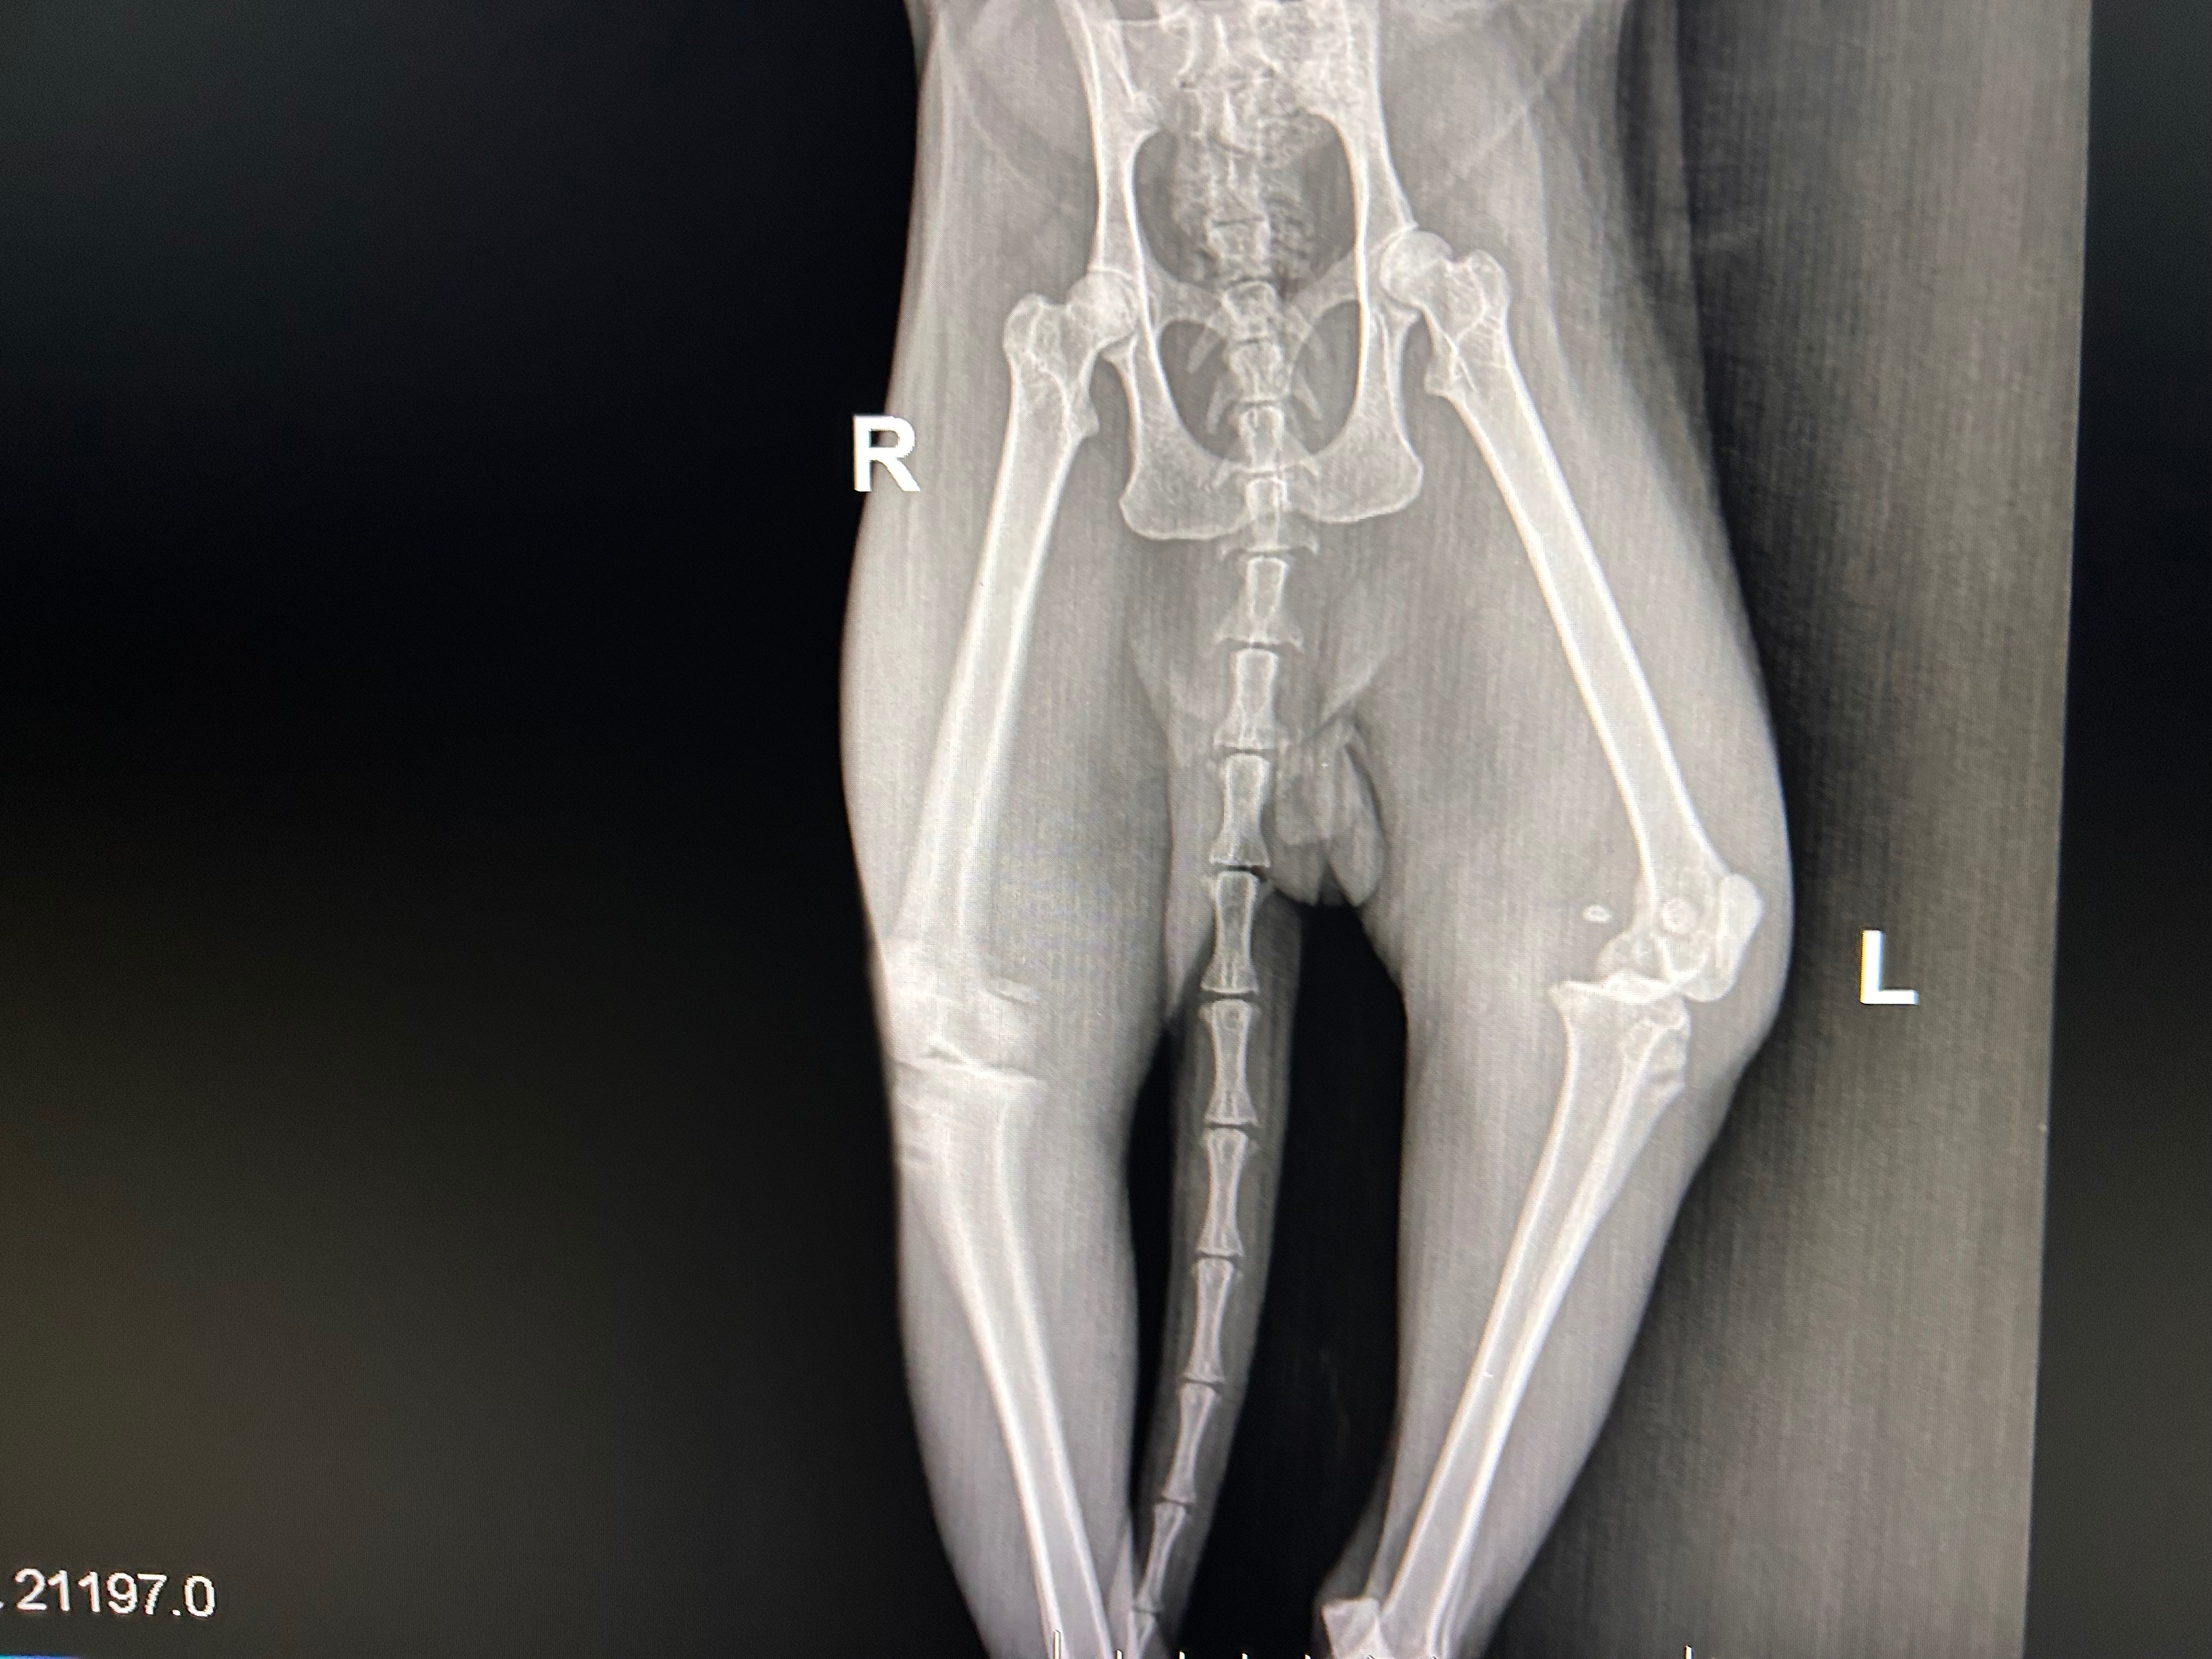

We brought him inside immediately and took him to the vet. His first visit cost $400, and the second visit cost $700, which included X-rays and additional exams. After reviewing the results, the vet strongly recommended that Misha be seen by an orthopedic specialist. Unfortunately, the only option to relieve his pain and give him a good quality of life is leg amputation.